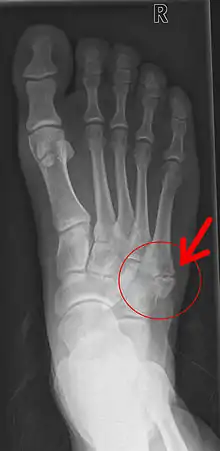

- Fractura de metatarsiano.